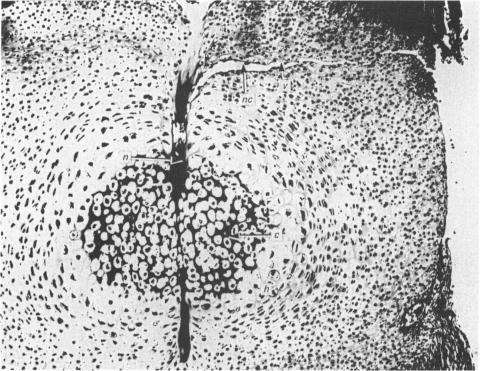

Bone formation in the vertebral centra commences within the centrum and is in this respect analogous to the secondary ossification which occurs in the epiphysis of a long bone. Bone tissue first appears at about the 85 mm C.R. stage and not in the 55 mm C.R. length embryo; at the latter stage blood vessels and calcification alone were observed. The connective tissue cells within the cartilage canal appear to assist osteogenesis by providing osteogenic cells which lay down bone in the walls of the cartilage canal, and provide cells which remove calcified cartilage found at the periphery of the canal; they assist growth by producing an appreciable number of chondrocytes that permit lateral expansion of the centra. Osteogenesis appears to occur in multiple foci within the growth plate of the older embryos and could account for the rapid rate of growth of vertebrae. Bone formation occurs in both mineralised and unmineralised matrix (as seen on the walls of the cartilage canals). The blood vessels within the growing vertebra tend to follow the zone of cartilage hypertrophy.